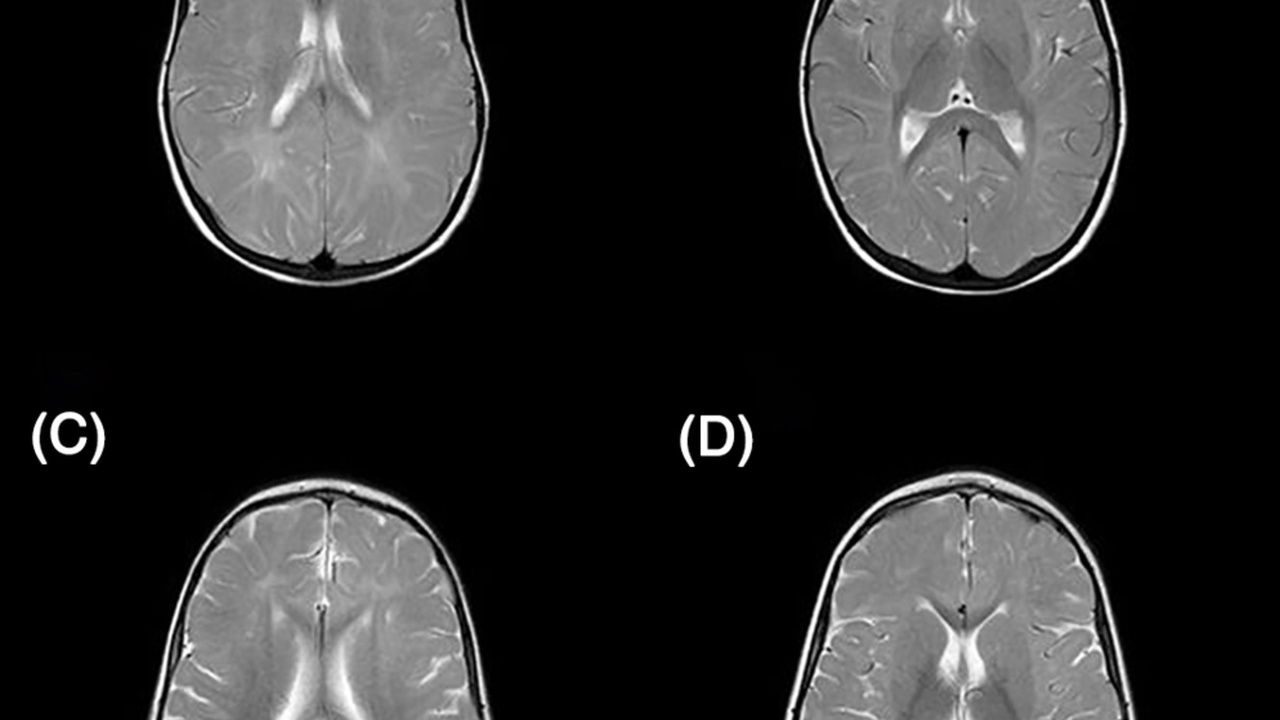

3. Brain volume changes, especially in the hippocampus

Certain brain regions shrink with age, and the hippocampus — a key structure for memory — is especially vulnerable. Longitudinal MRI studies that follow people for a decade or more report hippocampal shrinkage in the neighborhood of 1–2% per year in older adults.

Those volume changes correlate with memory performance and with higher risk of Alzheimer’s disease in those who show faster decline. Yet lifestyle factors matter: aerobic exercise, quality sleep, and cardiovascular risk control associate with better-preserved hippocampal volume in several longitudinal studies.

Put simply, brain structure is measurable and partly modifiable, so habits that protect cardiovascular health also support brain health.